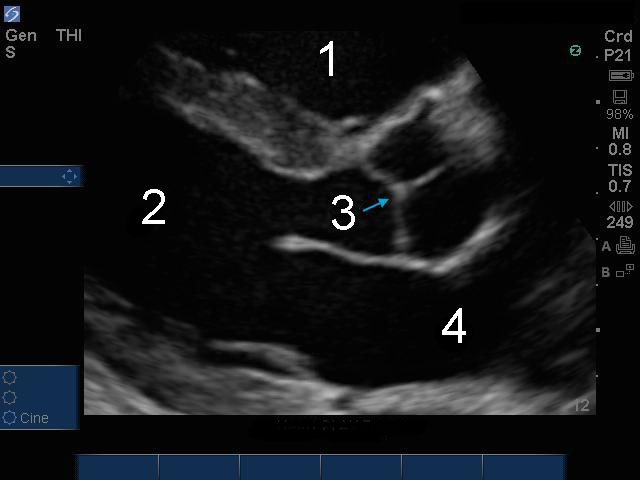

心脏胸骨旁长轴 (PLAX) 缩放图像

右心室 (RV)

左心室 (LV)

主动脉瓣 (AV)

左心房 (LA)